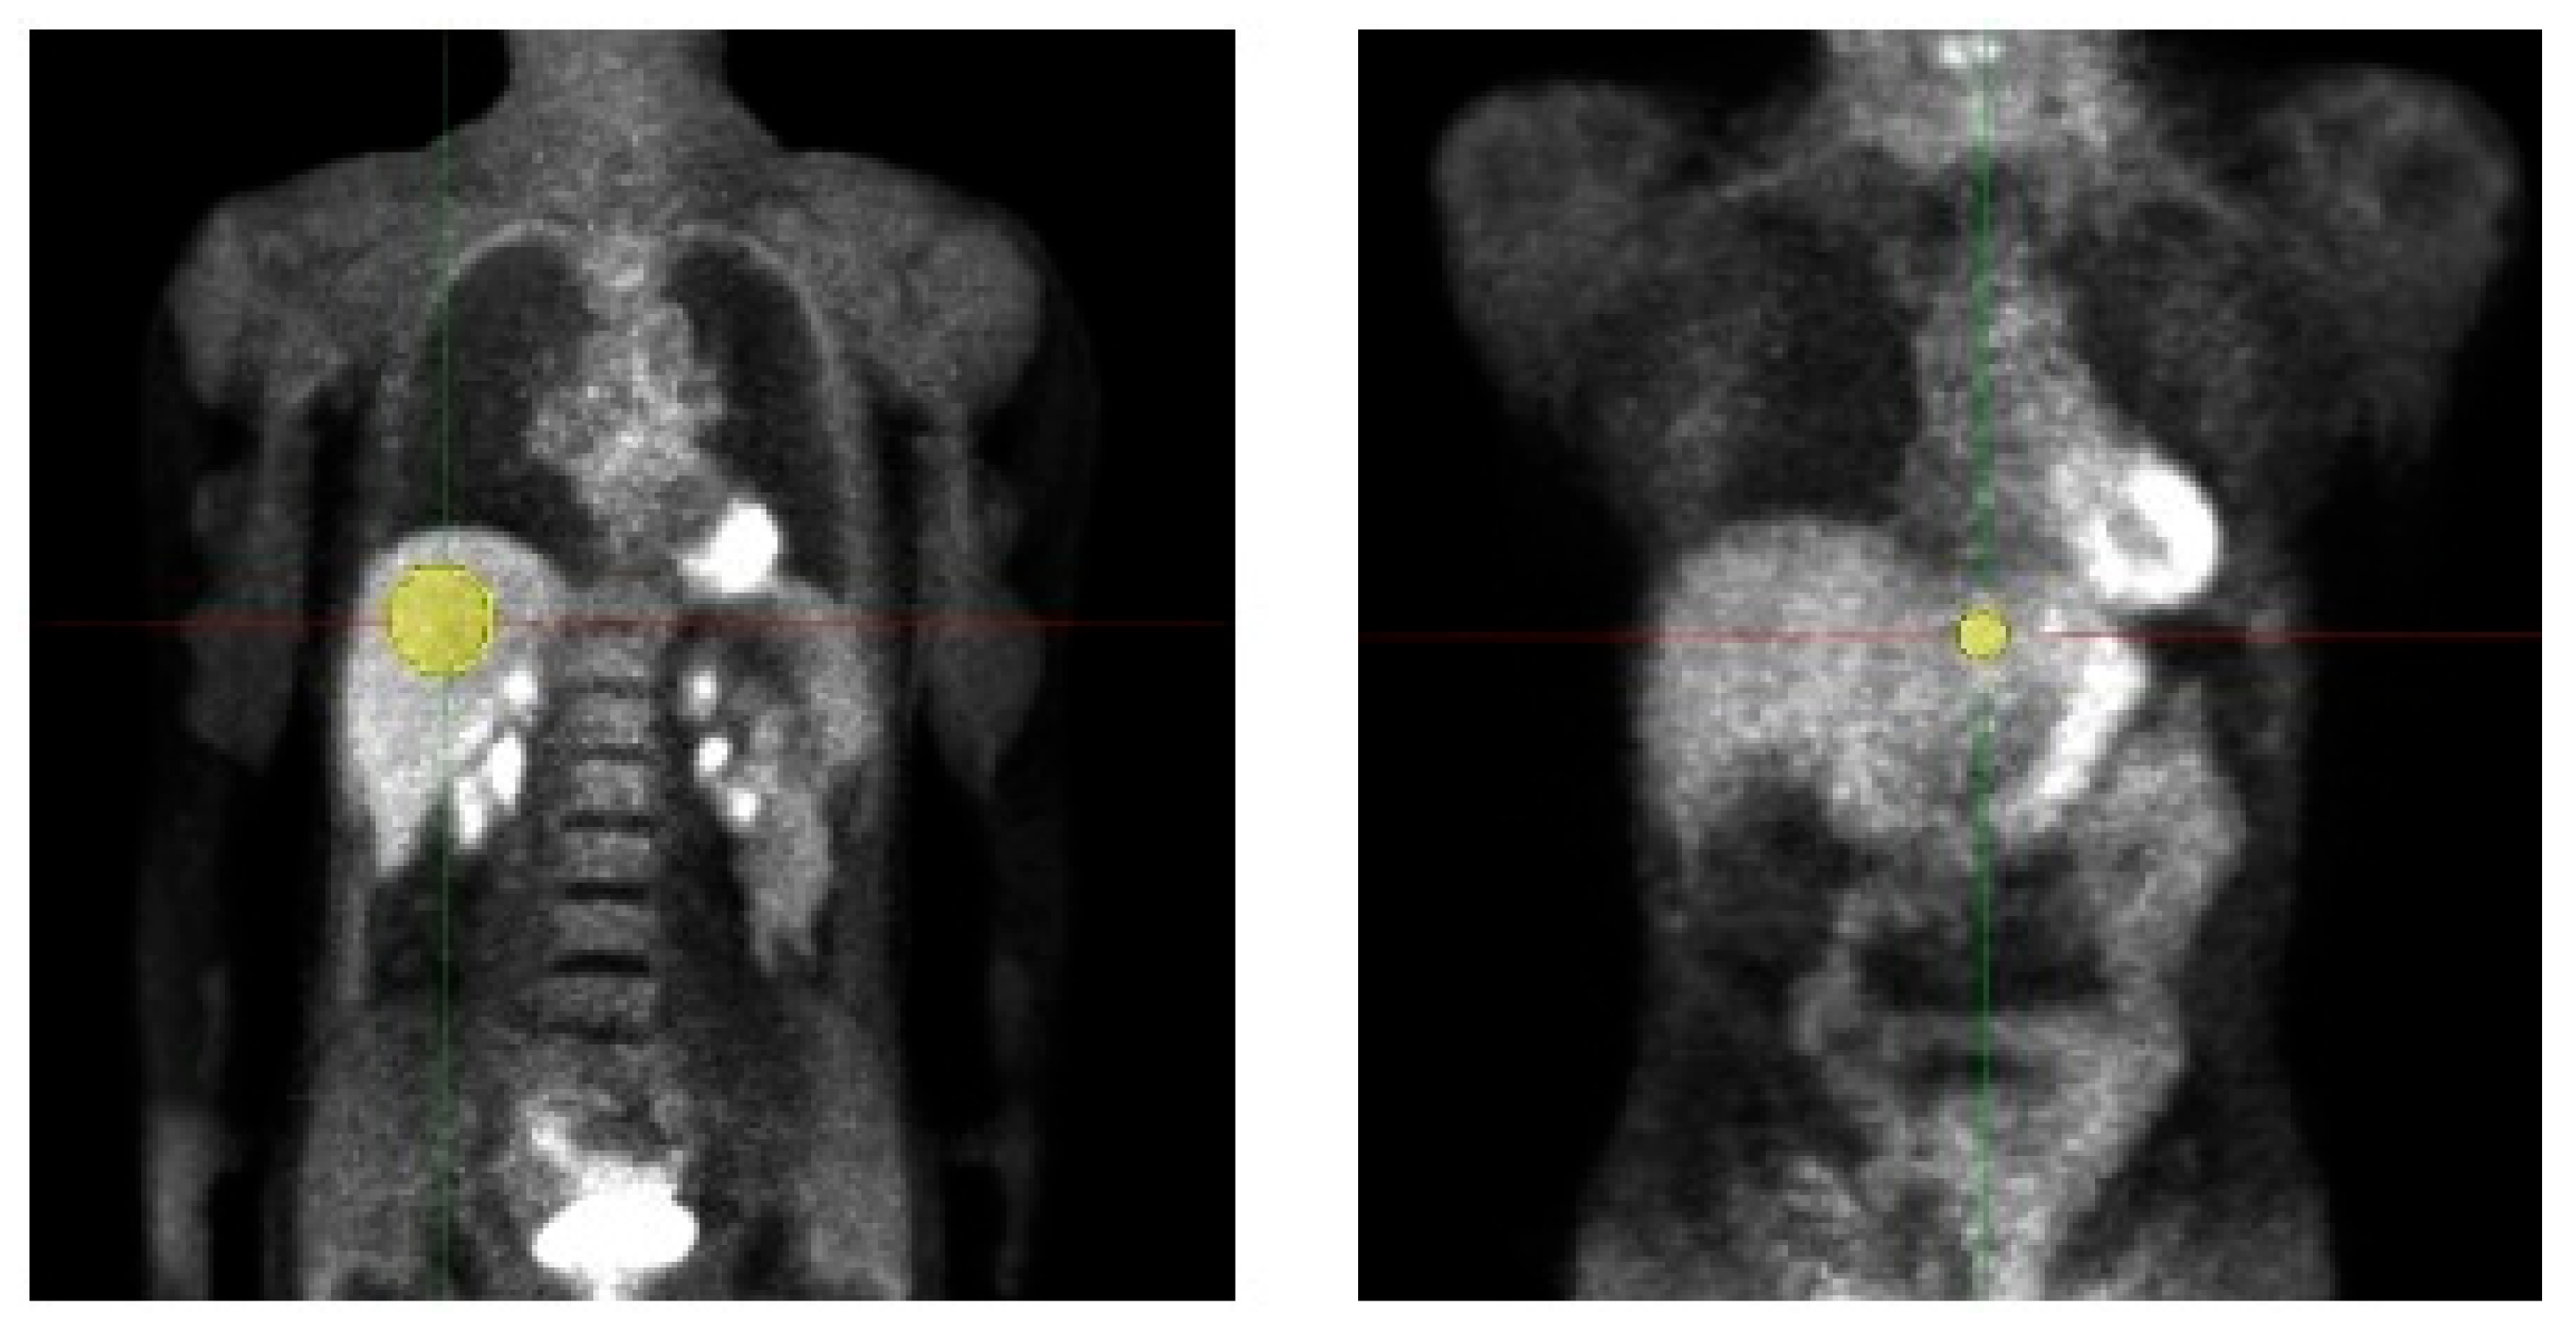

2.3. Patient Study

| Mask size [voxel] | 394 | VOI 1 (right liver lobe): 5866 ± 1676 VOI 2 (left liver lobe): 223 ± 57 |